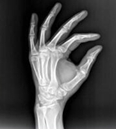

摘要:醫(yī)學(xué)影像學(xué)作為醫(yī)學(xué)專業(yè)大類中的一門重要學(xué)科,在醫(yī)學(xué)領(lǐng)域占有重要地位。學(xué)習(xí)醫(yī)學(xué)影像學(xué)具有以下特點(diǎn)。 1、實(shí)踐性強(qiáng)。學(xué)習(xí)影像學(xué)必需借助機(jī)器或膠片了解各種影像學(xué)檢查方法,

1、實(shí)踐性強(qiáng)。學(xué)習(xí)影像學(xué)必需借助機(jī)器或膠片了解各種影像學(xué)檢查方法,學(xué)習(xí)必要的技術(shù)操作。應(yīng)重視每一個(gè)實(shí)訓(xùn)操作機(jī)會,多動腦多動手,在老師指導(dǎo)下,掌握基本操作方法、程序和技能。

2、想象力強(qiáng)。醫(yī)學(xué)影像學(xué)是一門以圖像為基礎(chǔ)的專業(yè)課,學(xué)習(xí)過程中主要是通過觀察大量的圖片培養(yǎng)分析問題、處理問題的能力。學(xué)生必須學(xué)會對影像圖像的直觀認(rèn)識、三維空間思維,建立起各種影像間的立體聯(lián)系,可大大增強(qiáng)對疾病多方面影像的認(rèn)識能力。對將來閱讀CT、DSA(數(shù)字減影血管造影)、MRI片和超聲聲像圖大有裨益。

3、范疇廣泛。醫(yī)學(xué)影像學(xué)所涉及的臨床學(xué)科廣泛,涉汲檢查技術(shù)比較多,與人體解剖學(xué)、生理學(xué)、病理學(xué)、電子電工學(xué)、臨床醫(yī)學(xué)、醫(yī)學(xué)心理學(xué)等相關(guān)學(xué)科密切相關(guān)。只有學(xué)好本專業(yè)實(shí)際工作所必需的基礎(chǔ)醫(yī)學(xué)與臨床醫(yī)學(xué)的基本理論和基本知識,掌握常見病、多發(fā)病的診療規(guī)律掌握醫(yī)學(xué)影像專業(yè)的基本理論和基本技能,才能在將來工作中正確應(yīng)用影像學(xué)檢查結(jié)果為臨床診斷和治療服務(wù)。